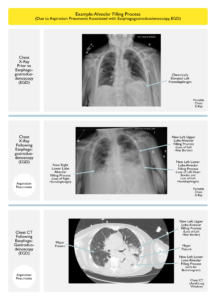

CXR-ALVEOLAR FILLING3